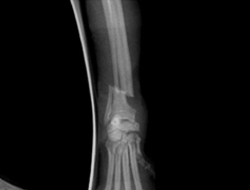

骨折

骨折手術にはプレート固定法、創外固定法、ピンニング法、インターロッキング法と各器具があり、骨折の状態により、手術法を検討し実施しています。

当院での骨折の手術症例

癒合不全